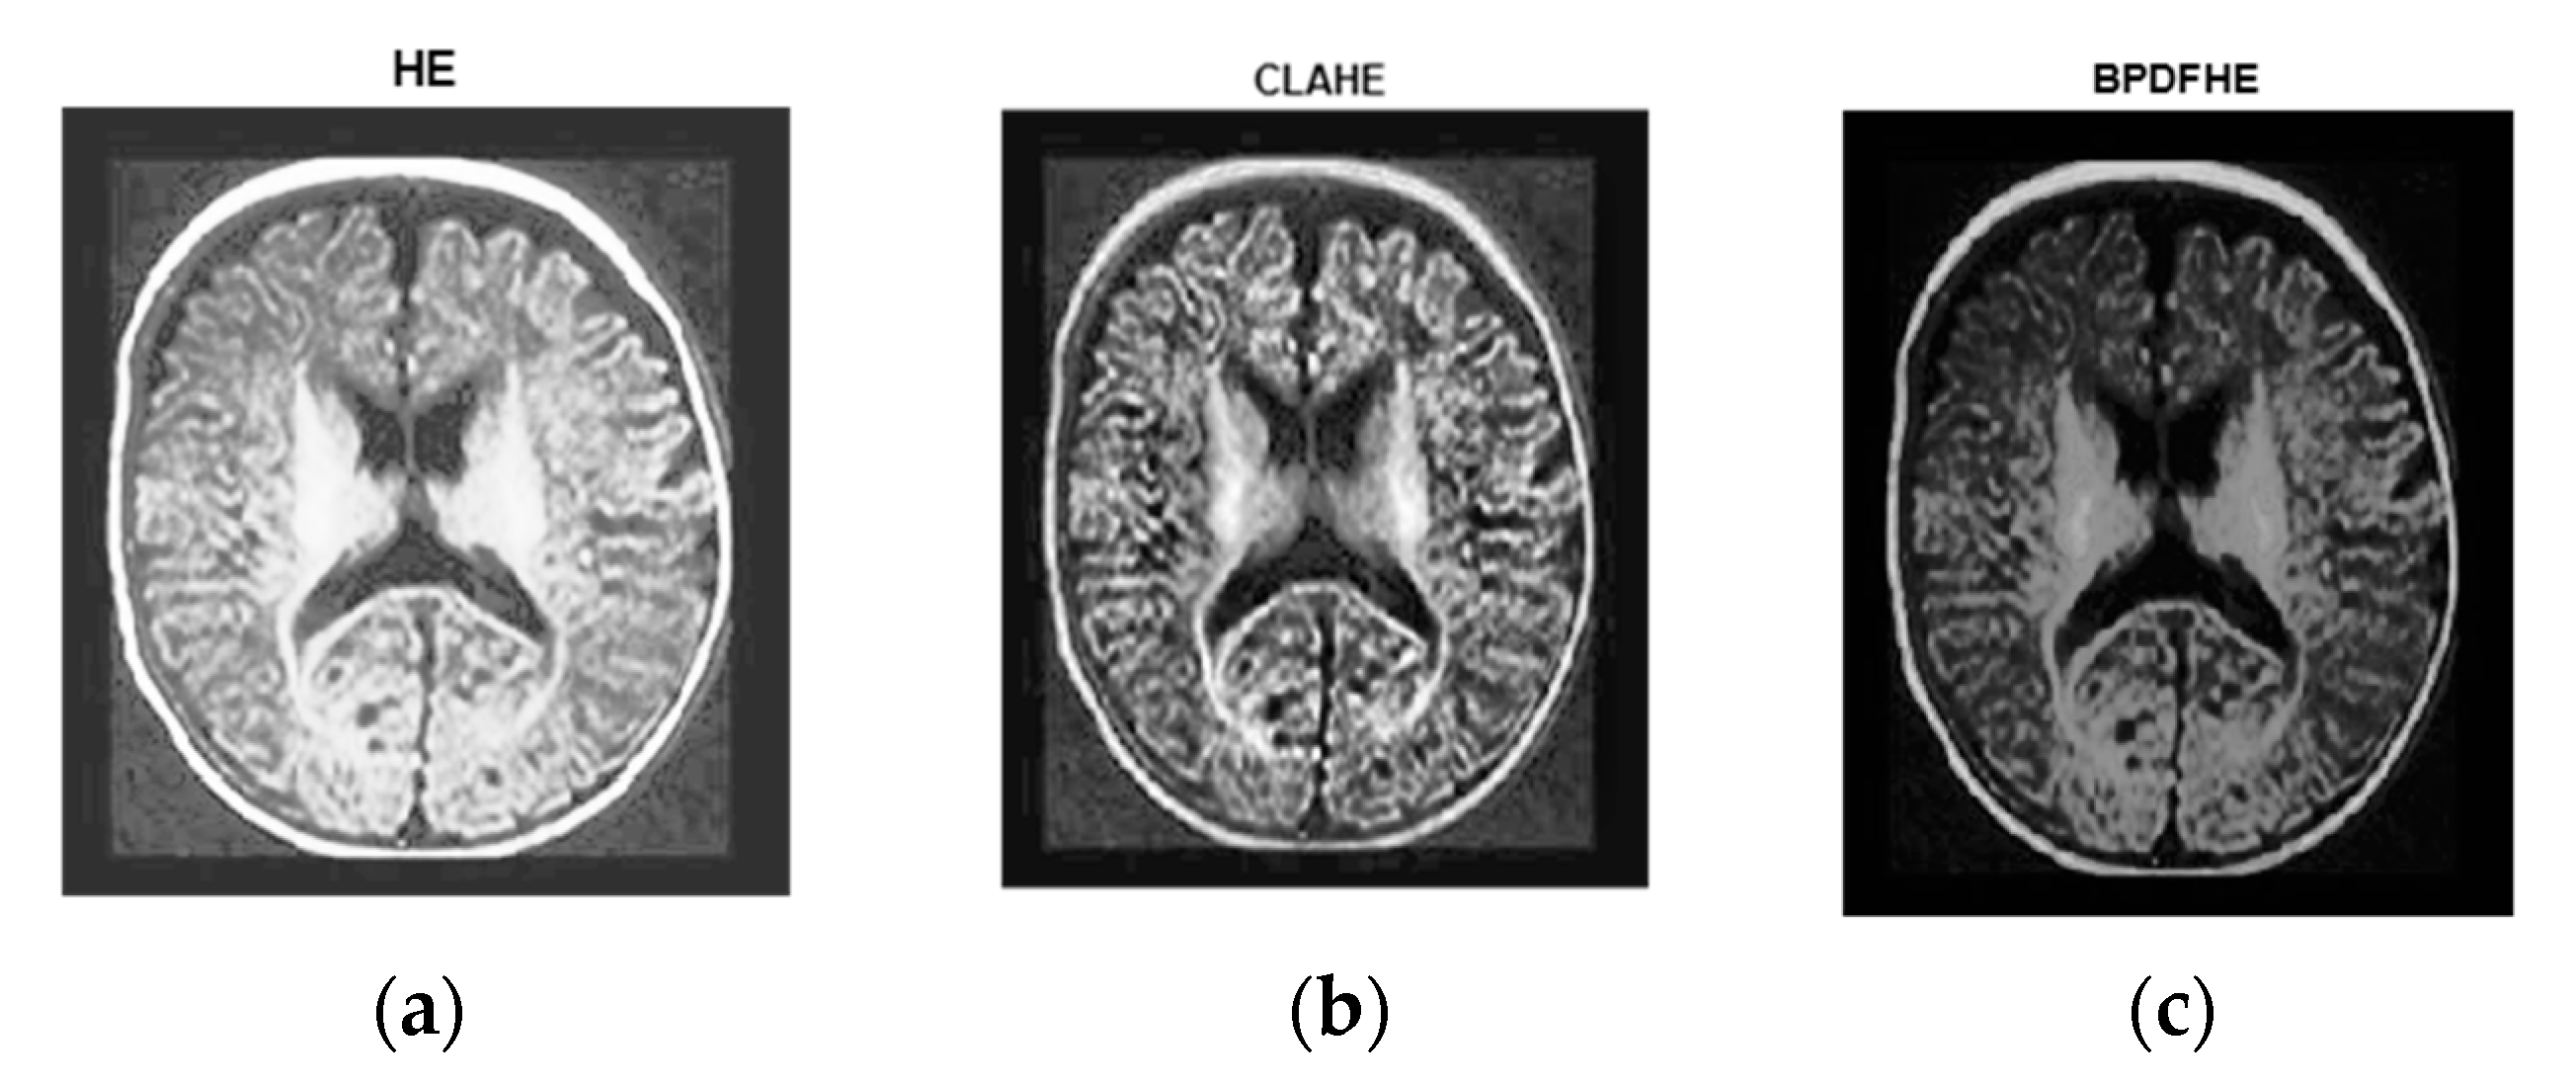

Figure 7a is the original image. Figure 7b is its histogram representation. Figure 8a–c represents the same image enhanced via different preprocessing methods, i.e., HE, CLAHE, BPDFHE, and Figure 9a–c is their respective histograms.

Figure 8.

Preprocessed with (a) HE, (b) CLAHE, and (c) BPDFHE.

Figure 9.

Histograms of preprocessed images of Figure 8. (a) HE, (b) CLAHE, and (c) BPDFHE.